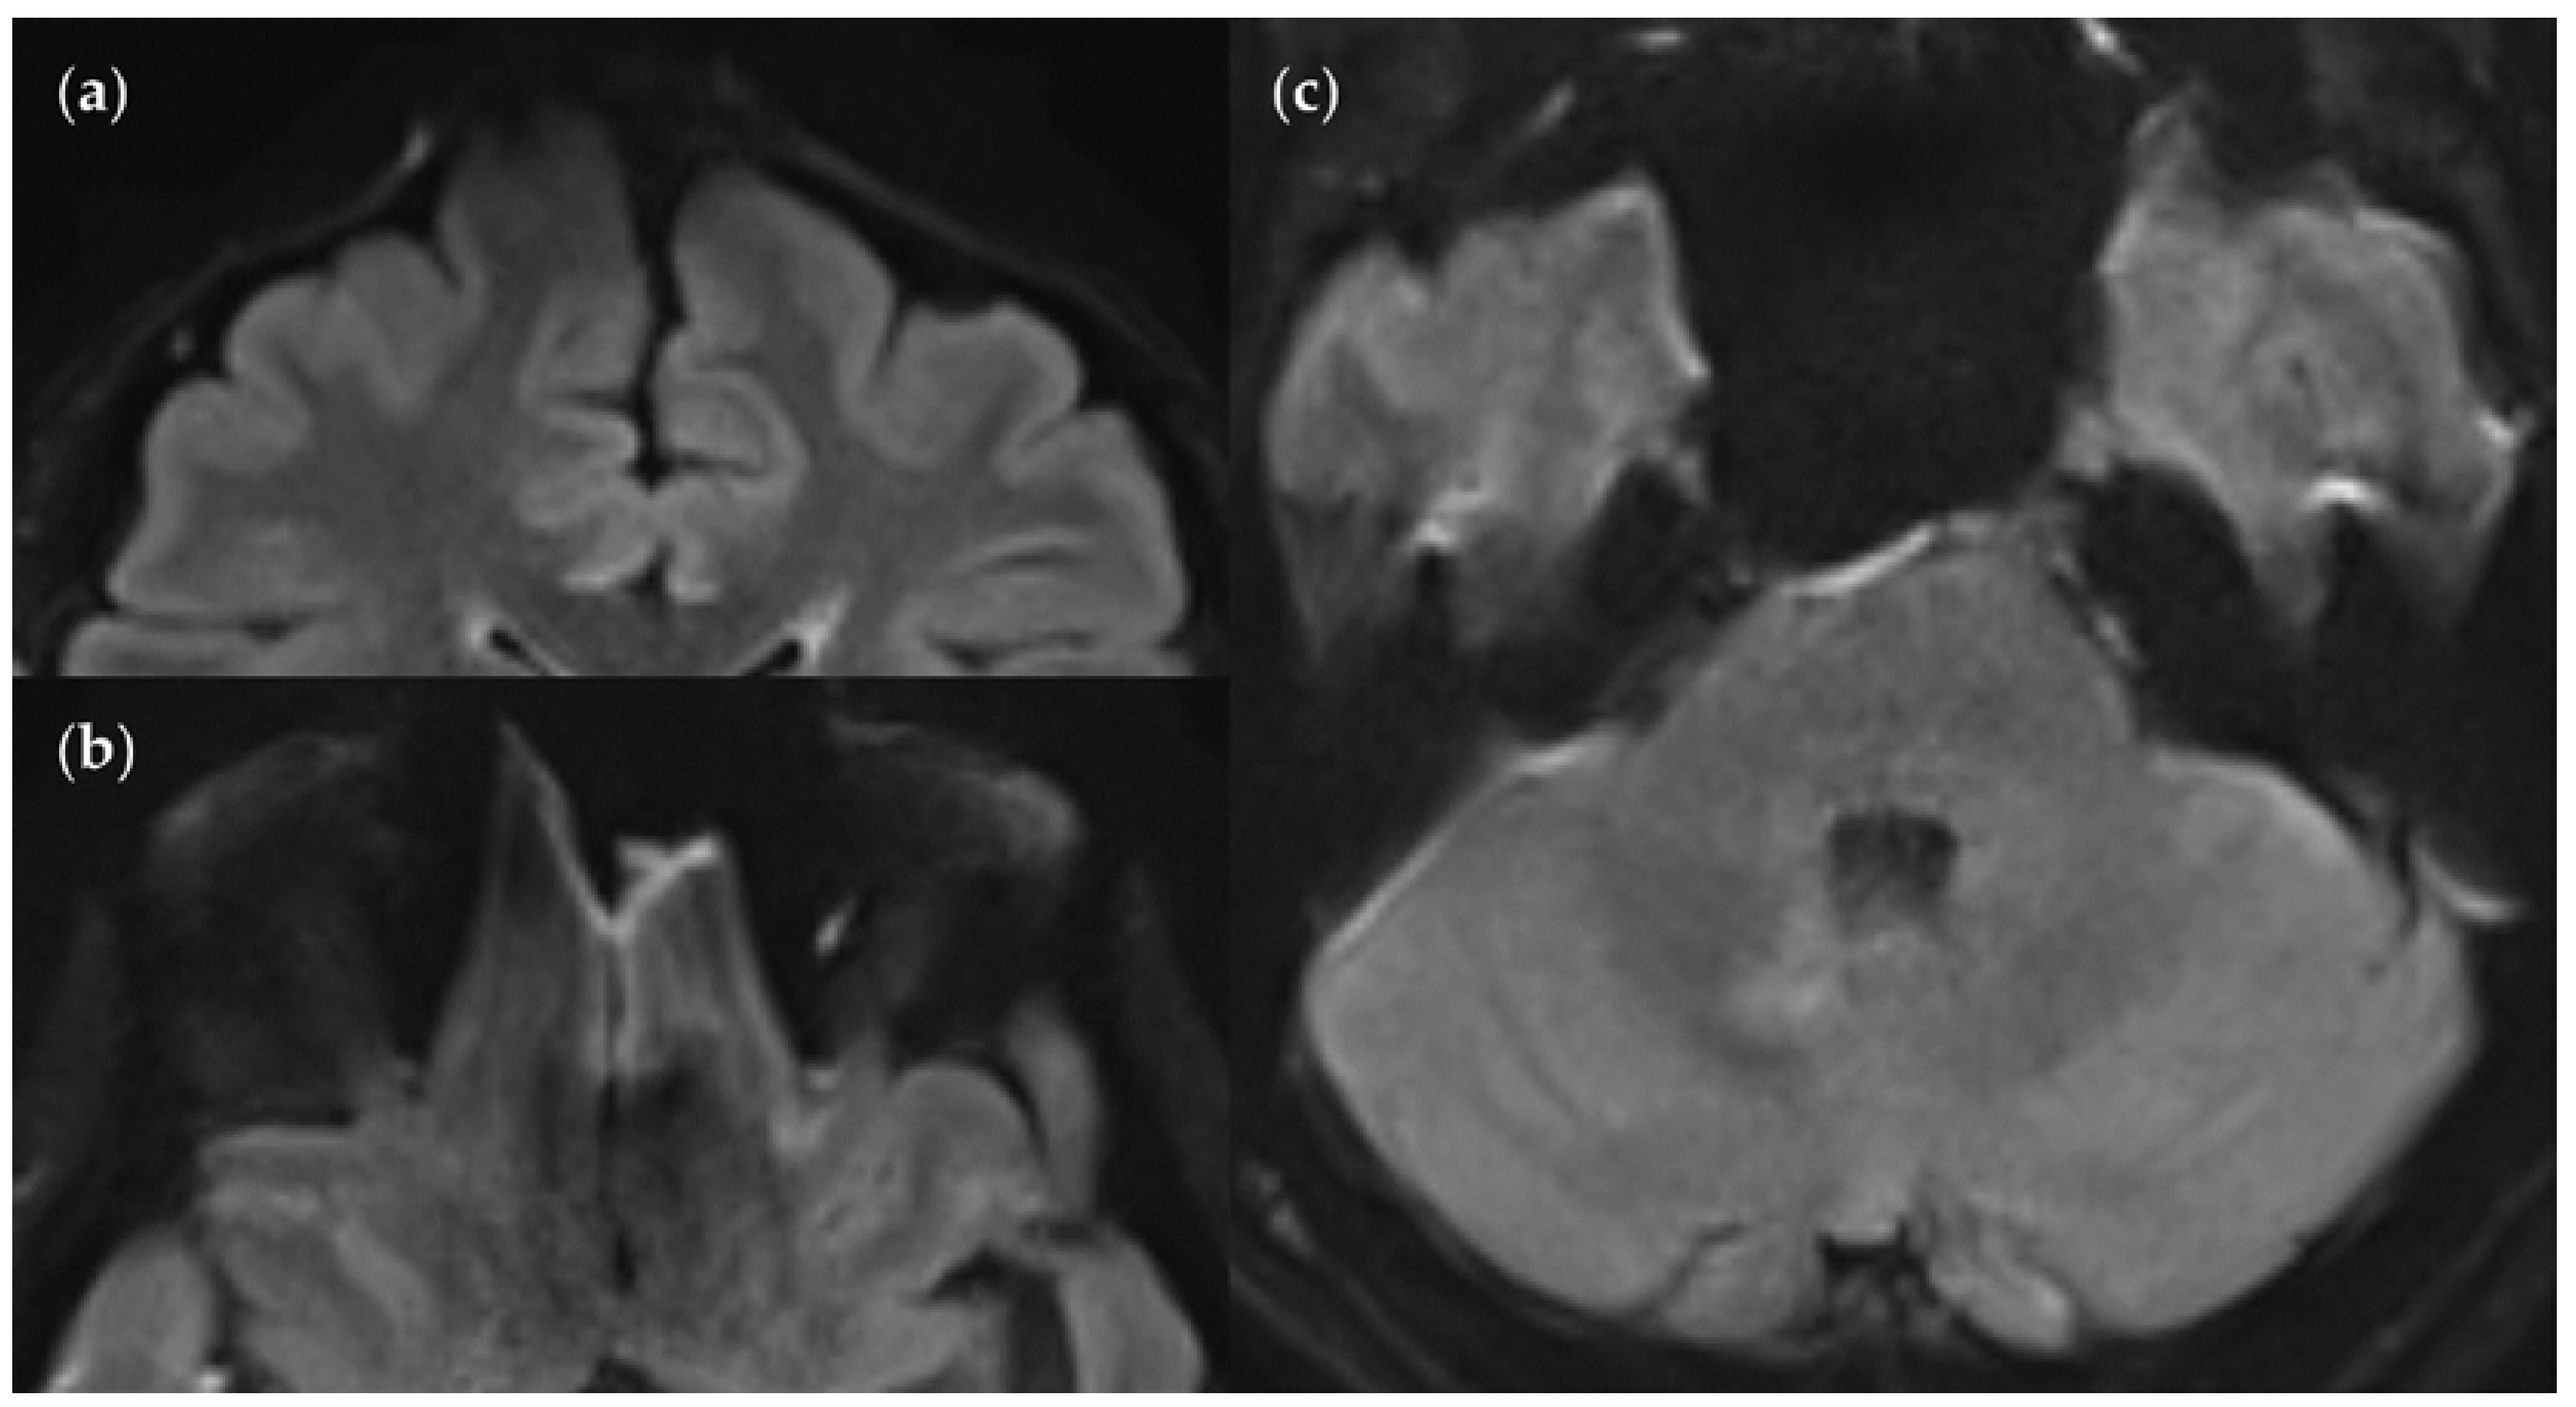

An MS patient received an MRI scan including three T2w FLAIR sequences: FLAIRUF (a), FLAIRTSE (b) and FLAIR3D (c). Five lesions can be seen in each picture, situated in the frontoparietal region.

Figure 10.